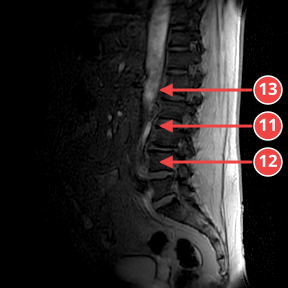

IMG-0001-00004.dcmSURVEY

Обзорная проекция с усилением лордоза. Снижение сигнала дисков L4-L5 и L5-S1 без значимой компрессии.

Аномалии

- [7] Снижение сигнала диска L4-L5 — medium — Дегидратация с умеренным снижением интенсивности T2. уверенность 70%